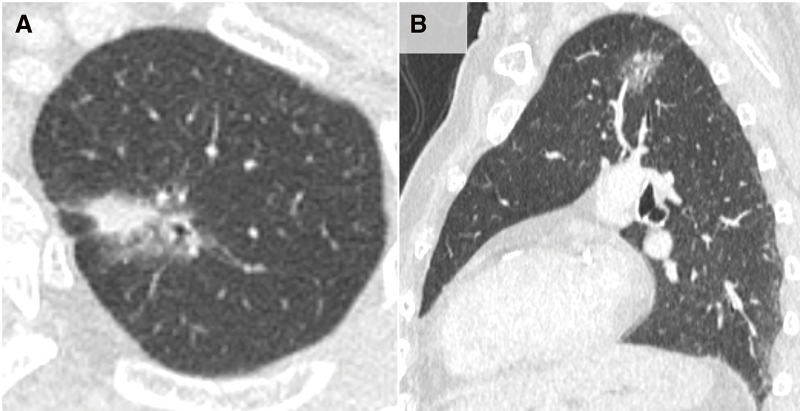

Case presentation: A female octogenarian presented for the treatment of simultaneous bilateral lung cancer. Three months after surgery for right lung cancer, a surgery for left lung cancer was performed. Preoperative computed tomography identified several broncho-arterial anomalies and a completely fused fissure, including a displaced left upper division bronchus and a pulmonary artery running anteriorly to the left main bronchus, similar to those in the right lung. Robotic left upper division segmentectomy with lymph node dissection was performed using a "hilum first, fissure last" approach with fine dissection of the hilar structures and minimal bleeding. The postoperative course was uneventful.